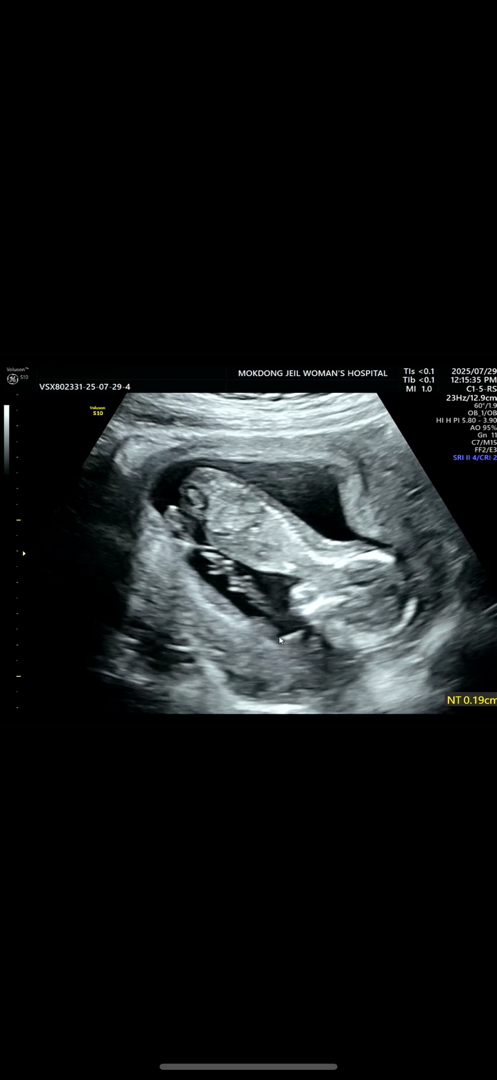

13주차 기형아 검진날 정밀초음파와 입체초음파도 진행했는데요 아기가 얼굴을 거꾸로 하고 있어서 그런지 원장님이 콧대 체크는 안해주신 것 같아서요 목투명대 체크는 해주셨는데~ 콧대 꼭 안봐도 되는건가요?

보통 코뼈도 성염색체 이상을 확인하는 중요한 요소중에 하나에용! 근데 아마 아가가 엎드려있으면 보일수가 없어서 못보신게 아닐까 싶으네요....